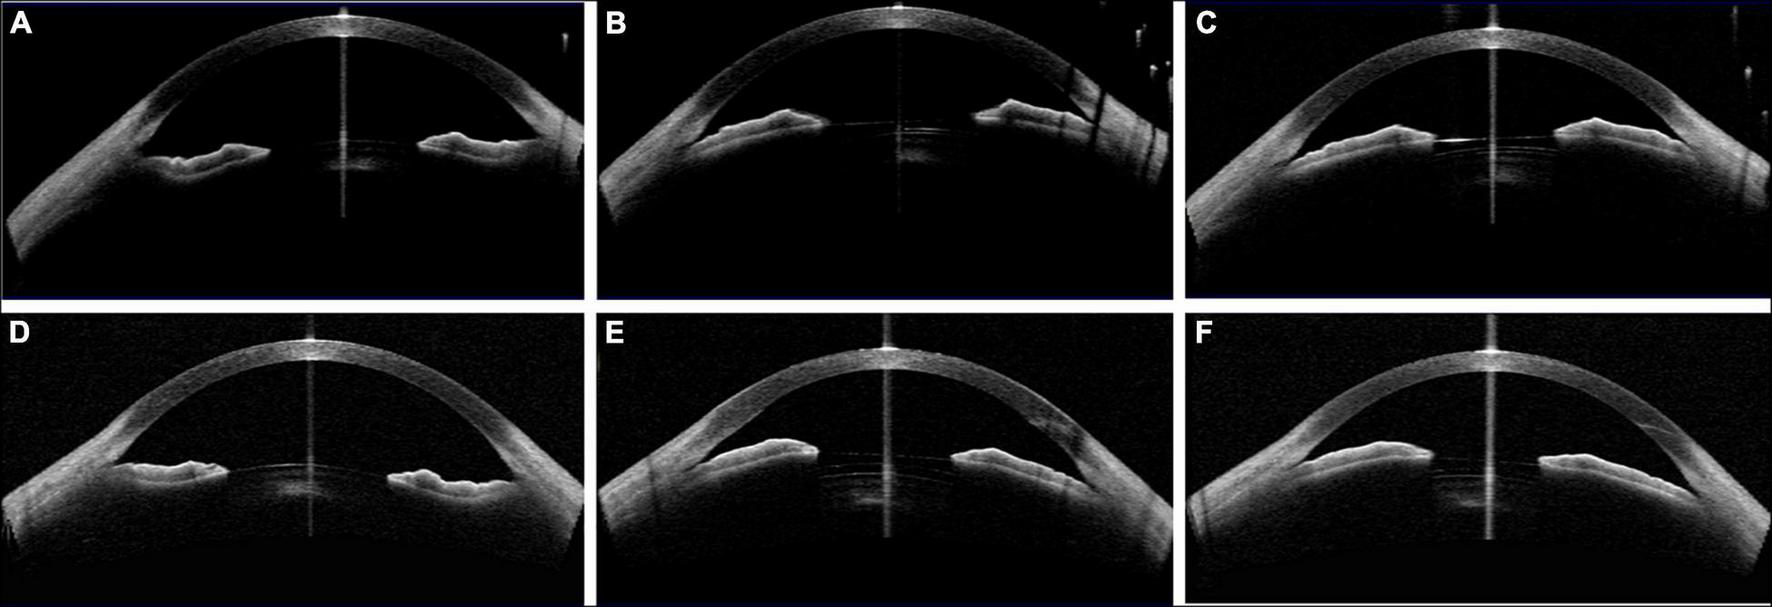

FIGURE 6

Case 3: (A,D) Concave shape iris before surgery; (B) low vault was shown 1 day postoperatively with 121 ICL; (C) the vault was slightly increased after ICL exchange into 126 ICL 1 month postoperatively; (E) the vault of the left eye was larger than that of the right eye with 126 ICL; (F) the vault decreased 1 month postoperatively. (Row 1: right eye; Row 2: left eye).

FIGURE 7

Case 4: (A,D) Convex shape iris before surgery; (B,E) 1 month after ICL implantation (B oblique position, E vertical position); (C) the vault value decreased after changing the ICL into a vertical position; (F) 2 month after ICL implantation. (Row 1: right eye; Row 2: left eye).